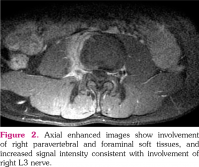

Lumbar vertebral computed tomography revealed a decrease in the right half of the disc height at the L3-4 intervertebral disc level (Figure 1a). Lumbosacral spinal magnetic resonance imaging (MRI) revealed in sagittal T2A sequences increased signal intensity, consistent with edema in the affected vertebrae and intervertebral disc (Figure 1b). The sagittal T1A sequences prior to contrast enhancement showed signal loss in the vertebral corpuses (Figure 1c), while sagittal postcontrast images showed a diffuse contrast uptake in the corresponding areas (Figure 1d). The axial postcontrast images showed involvement of the right paravertebral and foraminal soft tissues, and increased signal intensity consistent with the involvement of the right L3 nerve (Figure 2). Radiological findings were consistent with spondylodiscitis.